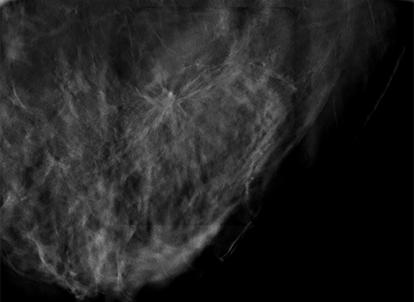

Superior imaging capability and a wider field of view.

With high quality 2D or tomosynthesis (3D™) imaging and a field of view that’s more than 6.5 times larger than older generations of prone biopsy systems,1 clinicians can visualize more tissue and pinpoint subtle lesions and faint calcifications that may not be visible on older systems. It also allows for easy software upgrade from 2D to 3D imaging at any time.